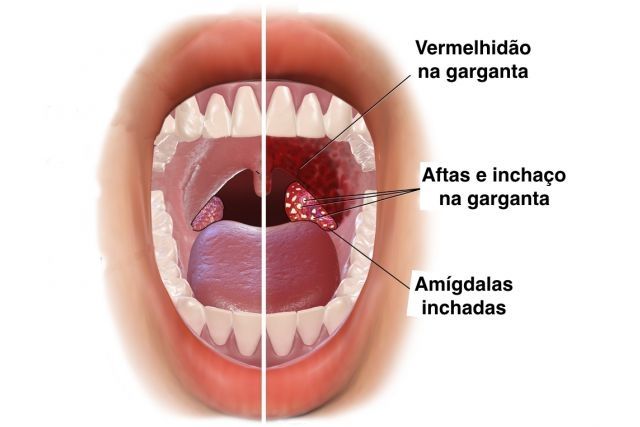

É normal sentir um leve desconforto, mas alguns sinais na sua garganta indicam que é hora de procurar um médico. Dor que não passa em uma semana, febre alta persistente ou dificuldade séria para engolir são sinais claros. Pus nas amígdalas ou irritação que dura mais de 15 dias também não devem ser ignorados. Fatores como fumar ou viver em locais poluídos podem agravar a situação e manter a garganta irritada por muito tempo.

É fundamental saber identificar quando a dor de garganta deixa de ser um incômodo comum e se torna algo que exige atenção médica. Procure ajuda profissional se você apresentar sinais de alerta na dor de garganta. Isso inclui dificuldade severa para engolir, febre alta que não cede, surgimento de pus nas amígdalas ou se a dor persistir por mais de uma semana.

Sintomas Graves e Preocupantes

Quando há febre alta e pus visível nas amígdalas, pode ser um sinal de infecção bacteriana, como a amigdalite estreptocócica. É importante procurar um médico para diagnóstico e tratamento adequados, pois pode ser necessário o uso de antibióticos. Fica tranquila, o especialista vai te orientar.

A dor de garganta viral geralmente vem acompanhada de outros sintomas como coriza e tosse, e melhora com repouso e hidratação. Já a dor de garganta bacteriana costuma ser mais intensa, com febre alta, dor ao engolir e, às vezes, presença de pus. Saber diferenciar é o primeiro passo para o tratamento correto.